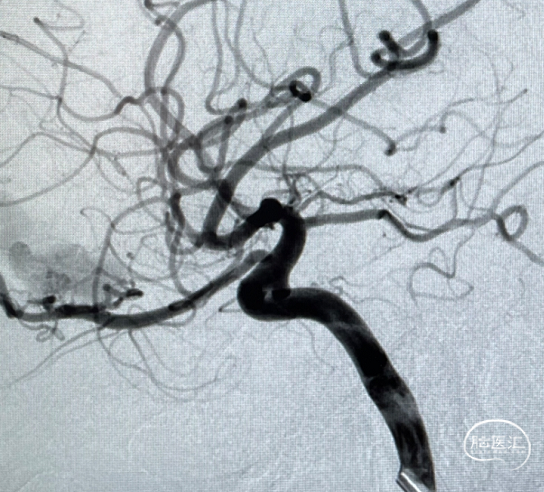

二期治疗